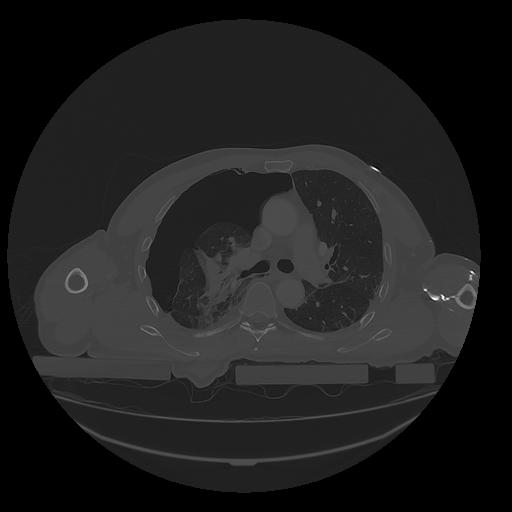

31 PULMON,CE,Vol,1.0,PULMON,,